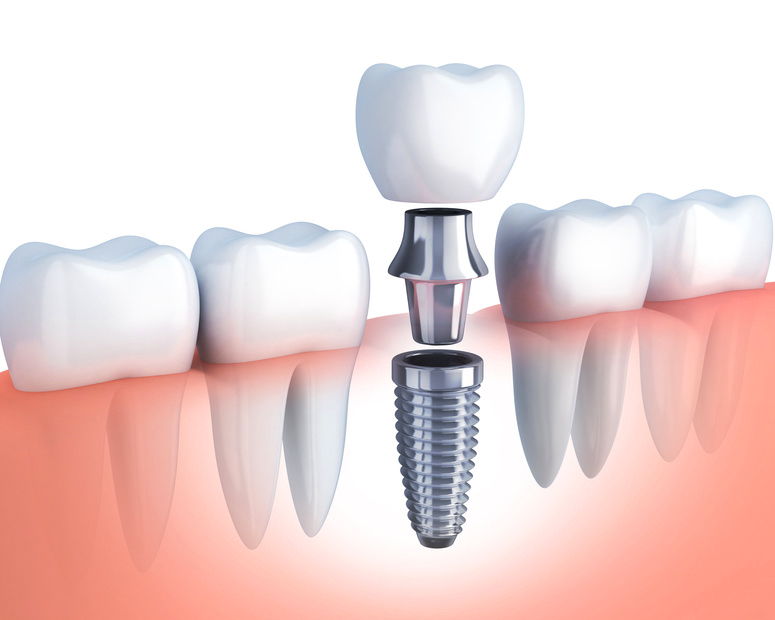

骨に直接、人工の歯の根っこを埋め込み、その上に人工の歯を被せる方法です。

残った歯に負担をかけないのが大きな特徴です。

周りの自分の歯を痛めず長持ちさせることにつながります。

固定されたしっかりとした義歯になりますので、お口の中がすっきりとし、自分の歯と同じような使用感が味わえ、安心してお食事ができるようになります。短所

高価です。外科手術になります。

インプラントが歯になじむまで3~6ヶ月かかります。